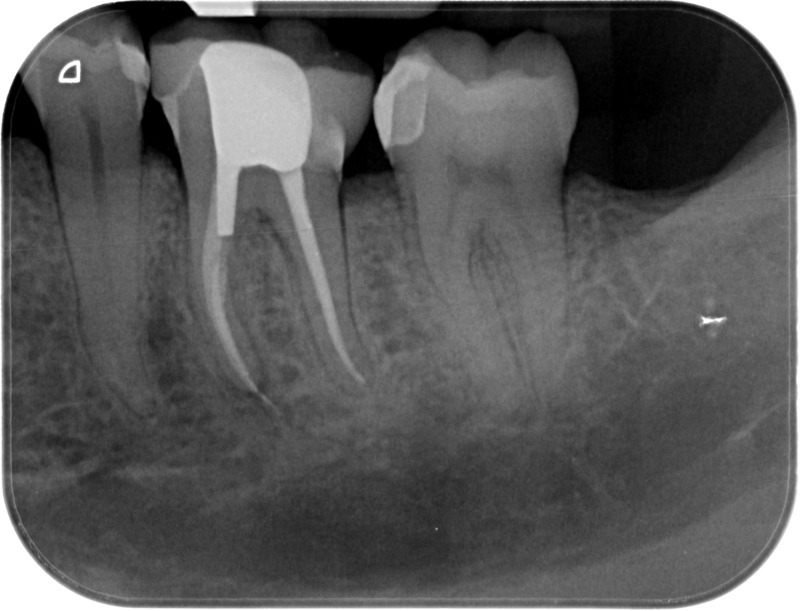

• Traitement endodontique : Sous anesthésie locale et à travers la protection d’un champ opératoire nous accédons à la pulpe de la dent à soigner, puis aux canaux de ses racines que nous devons désinfecter. Ce soin nécessite l’élimination complète de la source de contamination (souvent la carie) parfois sous une ancienne reconstitution ou une couronne qu’il faut alors retirer. Une fois le nettoyage et la mise en forme des canaux réalisés, nous les obturons de façon hermétique avec un ciment et un matériau thermoplastique appelé Gutta Percha. Ceci afin d’empêcher une nouvelle prolifération bactérienne et d’assurer le maintien de la dent dans ses structures de soutien (ligament parodontal et os alvéolaire). L’ouverture effectuée au centre de la dent sera d’abord refermée avec un pansement provisoire avant d’envisager ensemble la reconstitution d’usage : un composite, un inlay-onlay ou une couronne.

Avant

Après